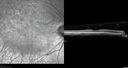

Sectoral Retinitis Pigmentosa - Asymptomatic263 views56-year-old female - The patient was in for an annual checkup because of her diabetes. No visual complaints (no night vision trouble)

293 Invitae genetic panel - negative     (0 votes)